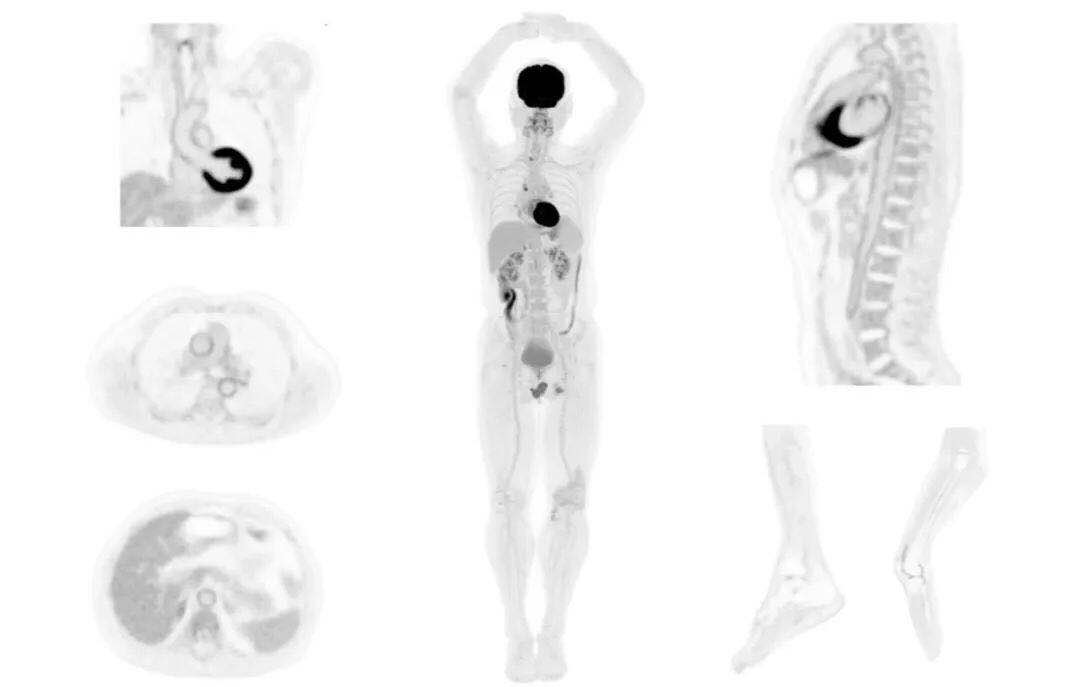

圖例

直腸癌

男,45歲,直腸癌術(shù)后9個(gè)月,發(fā)現(xiàn)肺占位

臨床診斷:直腸區(qū)術(shù)后改變,復(fù)發(fā)伴骶骨受累,雙肺多發(fā)轉(zhuǎn)移